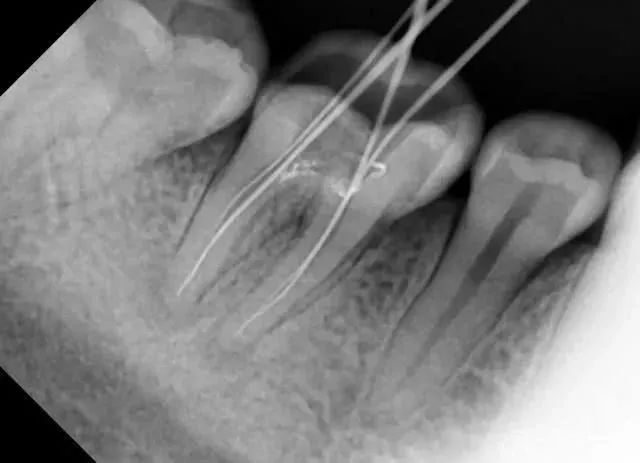

• 比如,当拔除下颌智齿时,仅凭口内检查无法发现它离神经管的位置

医生要判断牙槽骨是否符合种植条件,或者了解埋伏阻生齿的三维位置以及其他颌骨内病变组织的形态大小时,则需要进一步拍摄 CBCT 。

所以,拍牙片是一种帮助齿科医生进行诊断、治疗、疗效评估的重要手段,治疗前用于发现病变程度、范围;治疗中用于引导治疗、确定治疗范围和深度;治疗后用于观察疗效。